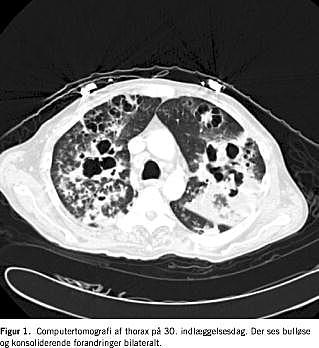

Efterforløbet var præget af respiratoriske komplikationer med bilateral pneumothorax. På dag 87 gik patienten ad mortem. På en computertomografi (CT) af cerebrum, thorax og abdomen foretaget under indlæggelsen sås bulløse og konso-liderende forandringer i begge lunger, ingen CT-påviselige abscesser i abdomen eller centralnervesystemet (Figur 1 ). Gentagne dyrkninger af blod, urin og trakealsekret gav ingen vækst af andre patogener. Hiv-test var negativ. Der blev ikke foretaget obduktion.